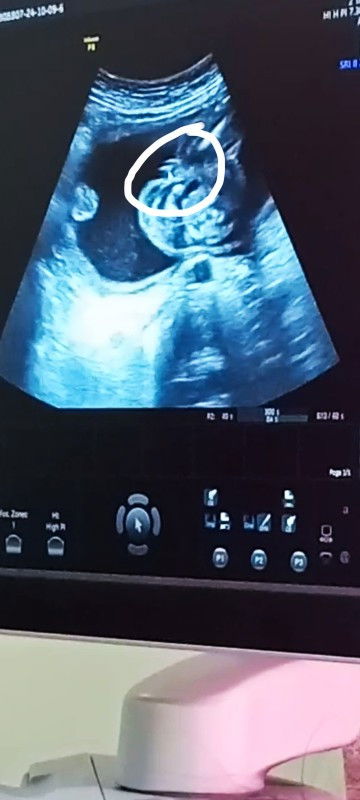

Gender ? Hi mga ka mommies🥰 Muka po bang 100% ng baby girl po nasa ultrasound ano po sa tingin nyo

Hi mga ka mommies🥰 Muka po bang 100% ng baby girl po nasa ultrasound ano po sa tingin nyo hihi🤗 Thanks ❤️ #respectpost

burger type yes girl hehehe